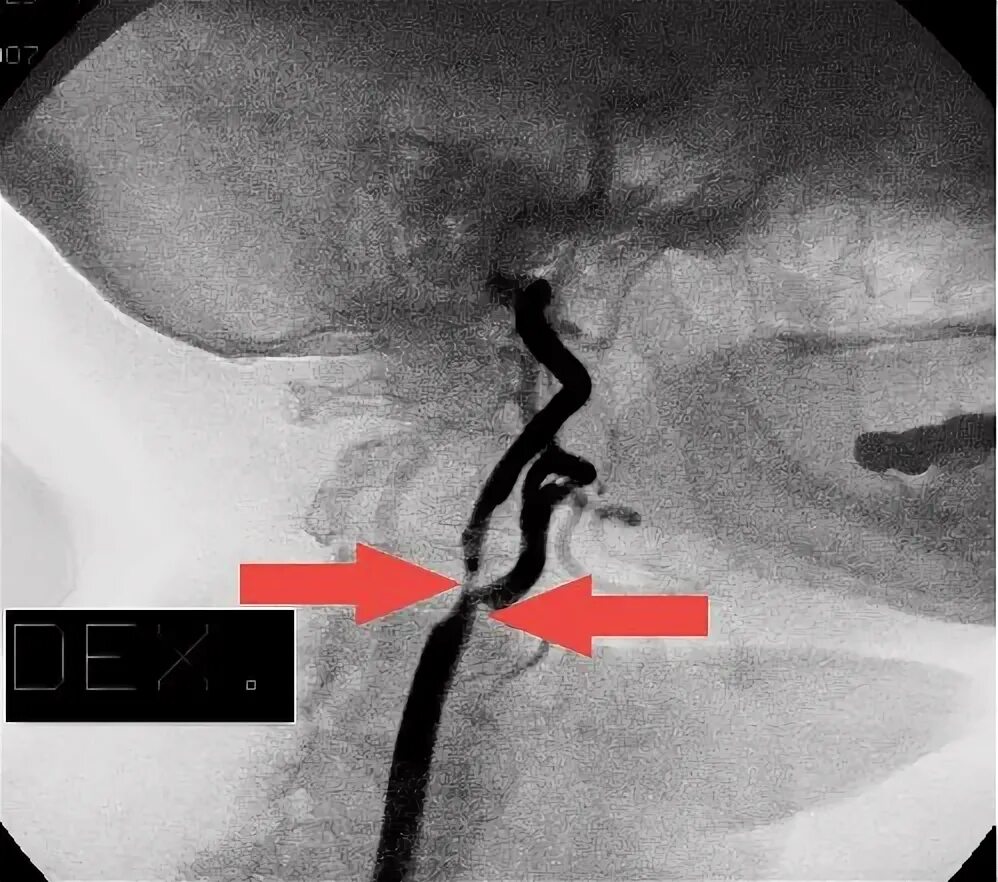

Атеросклероз шейных